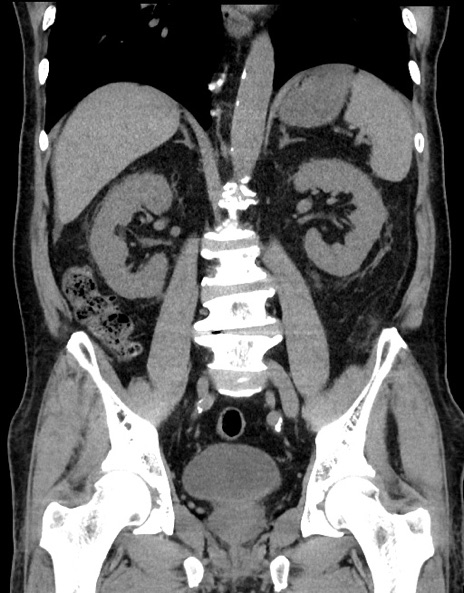

症例15(冠状断像)

【症例】70歳代男性

【主訴】腹痛

【現病歴】今朝から腹痛あり。全体的に痛い。特に左上の方。排ガスが今日はない。冷や汗が出る。

【既往歴】直腸癌術後

【身体所見】左側腹部〜上腹部に圧痛あり。腹膜刺激症状明らかなではない。軽度反跳痛。左下腹部に術後瘢痕あり。

【データ】WBC 7700、CRP 0.02